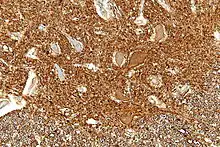

Numerous specific antibodies to neurofilament proteins have been developed and are commercially available. These antibodies can be used to detect neurofilament proteins in cells and tissues using immunofluorescence microscopy or immunohistochemistry. Such antibodies are widely used to identify neurons and their processes in histological sections and in tissue culture. The type VI intermediate filament protein Nestin is expressed in developing neurons and glia. Nestin is considered a marker of neuronal stem cells, and the presence of this protein is widely used to define neurogenesis. This protein is lost as development proceeds.

Neurofilament antibodies are also commonly used in diagnostic neuropathology. Staining with these antibodies can distinguish neurons (positive for neurofilament proteins) from glia (negative for neurofilament proteins).